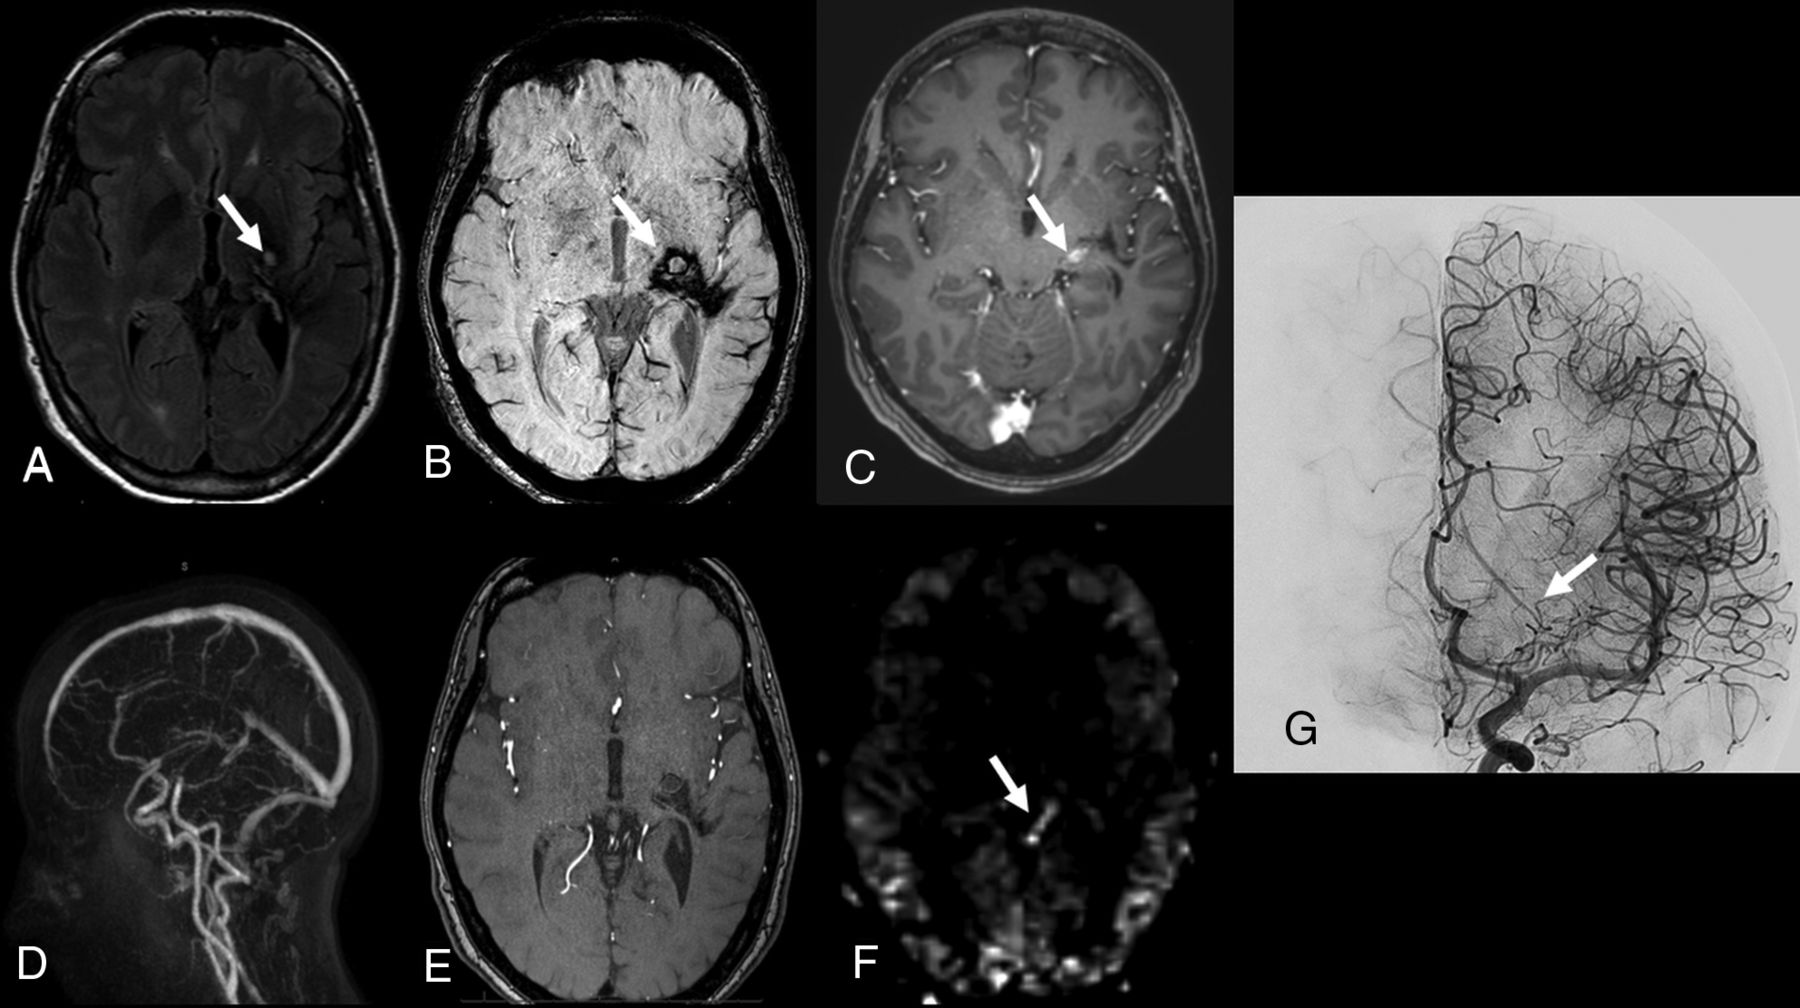

The sensitivity, specificity, positive predictive value, and negative predictive value of ASL/TOF for the detection of residual BAVMs were respectively 85% (95% CI, 62–97), 100% (95% CI, 63–100), 100% (95% CI, 80–100), and 73% (95% CI, 39–94). Individual results are described in Table 5. All residual BAVMs detected on ASL/TOF were confirmed on DSA. However, in 3 patients, while ASL/TOF findings were interpreted as negative, residual AVS was demonstrated on DSA. Of those 3 patients, imaging of 1 patient demonstrated faint hypersignal on ASL images at the site of the nidus, considered suggestive of a residual BAVM by all 3 readers; however, the lack of signal abnormality on anatomic MR images prevented the readers, who were blinded to the BAVM location, from detecting the nidus site (Fig 4). Comparison of TOF and ASL ratings showed that all residual BAVMs and nidus obliterations detected on TOF images were correctly classified on ASL images. In 3 patients with negative findings on TOF images, ASL showed the presence of a residual AVS in 2 patients and a 5-mm residual BAVM in 1 patient (Fig 2).

Patient 9. Follow-up MR imaging 6 years after radiosurgery for an unruptured left posterior temporal brain AVM. T1-weighted noncontrast (A), SWI (B), postcontrast 3D T1 GRE (C), 4D contrast-MRA (D), and a source image from 3D-TOF (E) do not show signal abnormality. F, ASL shows faint hyperintense signal (arrow) not interpreted as a residual BAVM by the 3 readers who were blinded to the BAVM location. G, DSA with a sagittal intracranial view from a superselective left temporal artery angiogram shows an early superficial draining vein contrast filling (arrow).